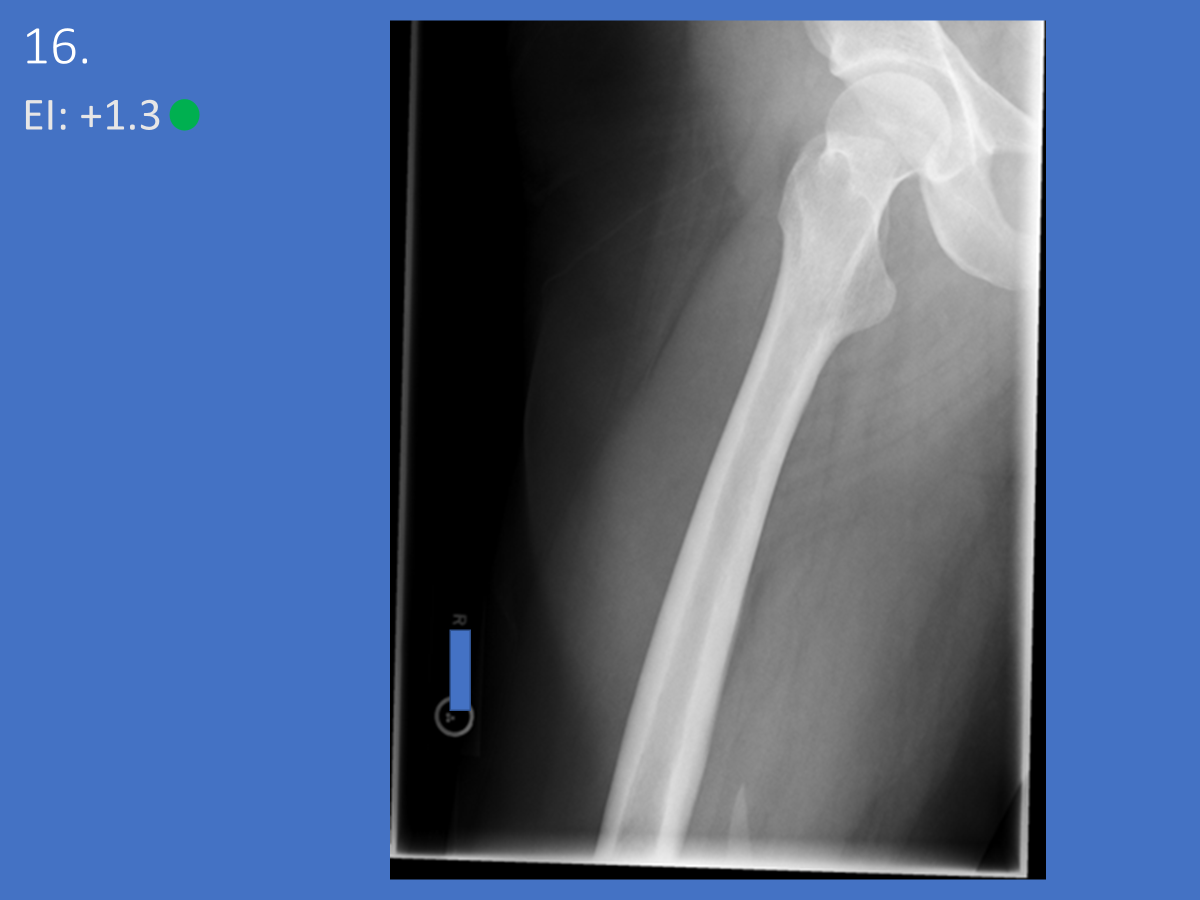

AP Femur

•Evidence of proper collimation and the presence of a side marker placed clear of the anatomy of interest

•Most of the femur and the joint nearest to the pathologic condition or site of injury (a second projection of the other joint is recommended)

•Femoral neck not foreshortened on the proximal femur

•Lesser trochanter not seen beyond the medial border of the femur or only a very small portion seen on the proximal femur

•No knee rotation on the distal femur

•Gonad shielding when indicated, but without the shield not covering proximal femur

•Any orthopedic appliance in its entirety

•Bony trabecular detail and surrounding soft tissues

Lesser trochanter is on, leg is not rotated in, under-rotated, hanging out too laterally

Leg was not internally rotated

No repeat, lesser trochanter can hardly see

Missing anatomy

slight medial rotation